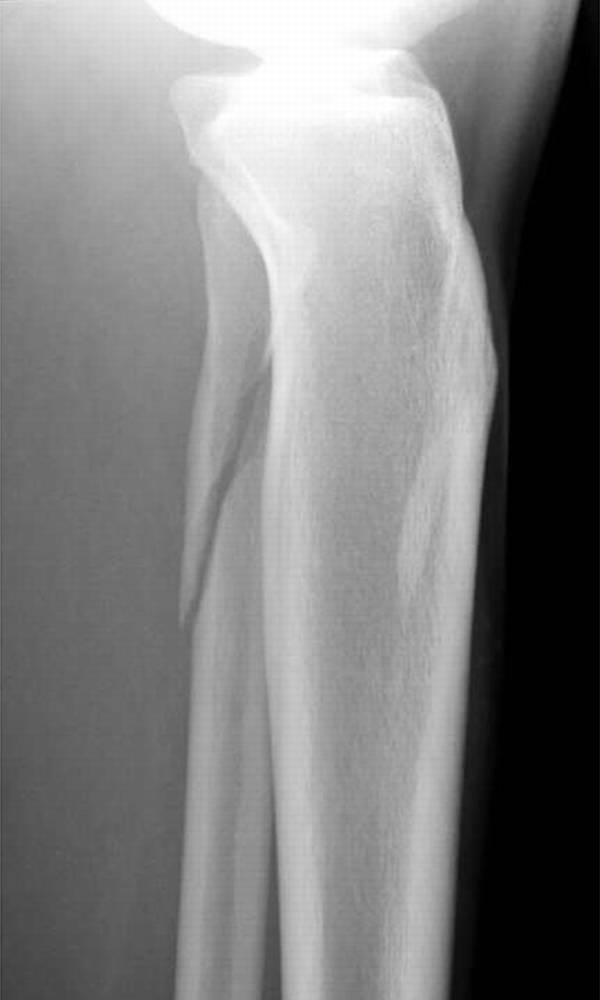

在脚踝处,必须警惕超出投照视野(图4)的足部腓骨骨折的可能性和足部骨折的可能性。例如,Maisonneuve骨折是一种旋前 - 旋转损伤,伴有远端胫腓骨间继位断裂和近端腓骨骨折[19]。了解骨折模式与相关的损伤机制模式至关重要,特别是在踝关节[20]。

图。4A-28岁女子在地面跌倒后。A,踝关节的斜视图显示继发性加宽和微小的内侧踝撕裂性骨折。B,近侧腿的侧视图显示倾斜的近端腓骨骨折,构成Maisonneuve骨折。